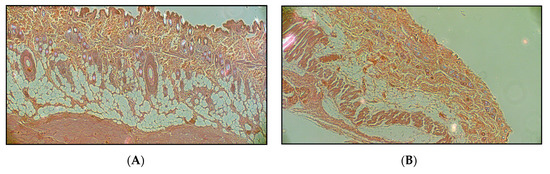

Structural and Functional Analysis of Excised Skins and Human Reconstructed Epidermis with Confocal Raman Spectroscopy and in Microfluidic Diffusion Chambers

by Dorottya Kocsis, Hichem Kichou, Katalin Döme, Zsófia Varga-Medveczky, Zsolt Révész, Istvan Antal and Franciska Erdő

Pharmaceutics 2022, 14(8), 1689; https://doi.org/10.3390/pharmaceutics14081689 - 13 Aug 2022

Several ex vivo and in vitro skin models are available in the toolbox of dermatological and cosmetic research. Some of them are widely used in drug penetration testing. The excised skins show higher variability, while the in vitro skins provide more reproducible data. [...] Read more.

Several ex vivo and in vitro skin models are available in the toolbox of dermatological and cosmetic research. Some of them are widely used in drug penetration testing. The excised skins show higher variability, while the in vitro skins provide more reproducible data. The aim of the current study was to compare the chemical composition of different skin models (excised rat skin, excised human skin and human-reconstructed epidermis) by measurement of ceramides, cholesterol, lactate, urea, protein and water at different depths of the tissues. The second goal was to compile a testing system, which includes a skin-on-a-chip diffusion setup and a confocal Raman spectroscopy for testing drug diffusion across the skin barrier and accumulation in the tissue models. A hydrophilic drug caffeine and the P-glycoprotein substrate quinidine were used in the study as topical cream formulations. The results indicate that although the transdermal diffusion of quinidine is lower, the skin accumulation was comparable for the two drugs. The various skin models showed different chemical compositions. The human skin was abundant in ceramides and cholesterol, while the reconstructed skin contained less water and more urea and protein. Based on these results, it can be concluded that skin-on-a-chip and confocal Raman microspectroscopy are suitable for testing drug penetration and distribution at different skin layers within an exposition window. Furthermore, obese human skin should be treated with caution for skin absorption testing due to its unbalanced composition. Full article